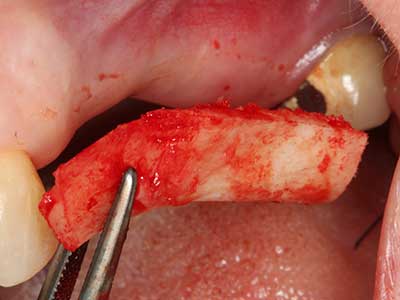

Bei der Knochenblockentnahme zeigen sich weitere Vorteile für die Piezochirurgie: Neben der bereits beschriebenen hohen Präzision bei der Osteotomie stellt sich gerade die Verwendung der dünnen Sägespitzen als besonders materialschonend heraus. Bei der Verwendung insbesondere von Lindemannfräsen sind mit deutlich höheren Entnahmeverlusten durch die dickere Instrumentenspitze zu rechnen (Lakshmiganthan, Gokulanathan et al. 2012). Die insbesondere bei retromolar entnommenen Blocktransplantaten notwendige basale Abtrennung wird durch speziell hierfür vorgesehene rechtwinklige Sägen erleichtert, so dass die Piezochirurgie als präzises, übersichtliches und sicheres Verfahren zur retromolaren Knochenblockgewinnung angesehen wird (Happe 2007) (Abb. 1-12).